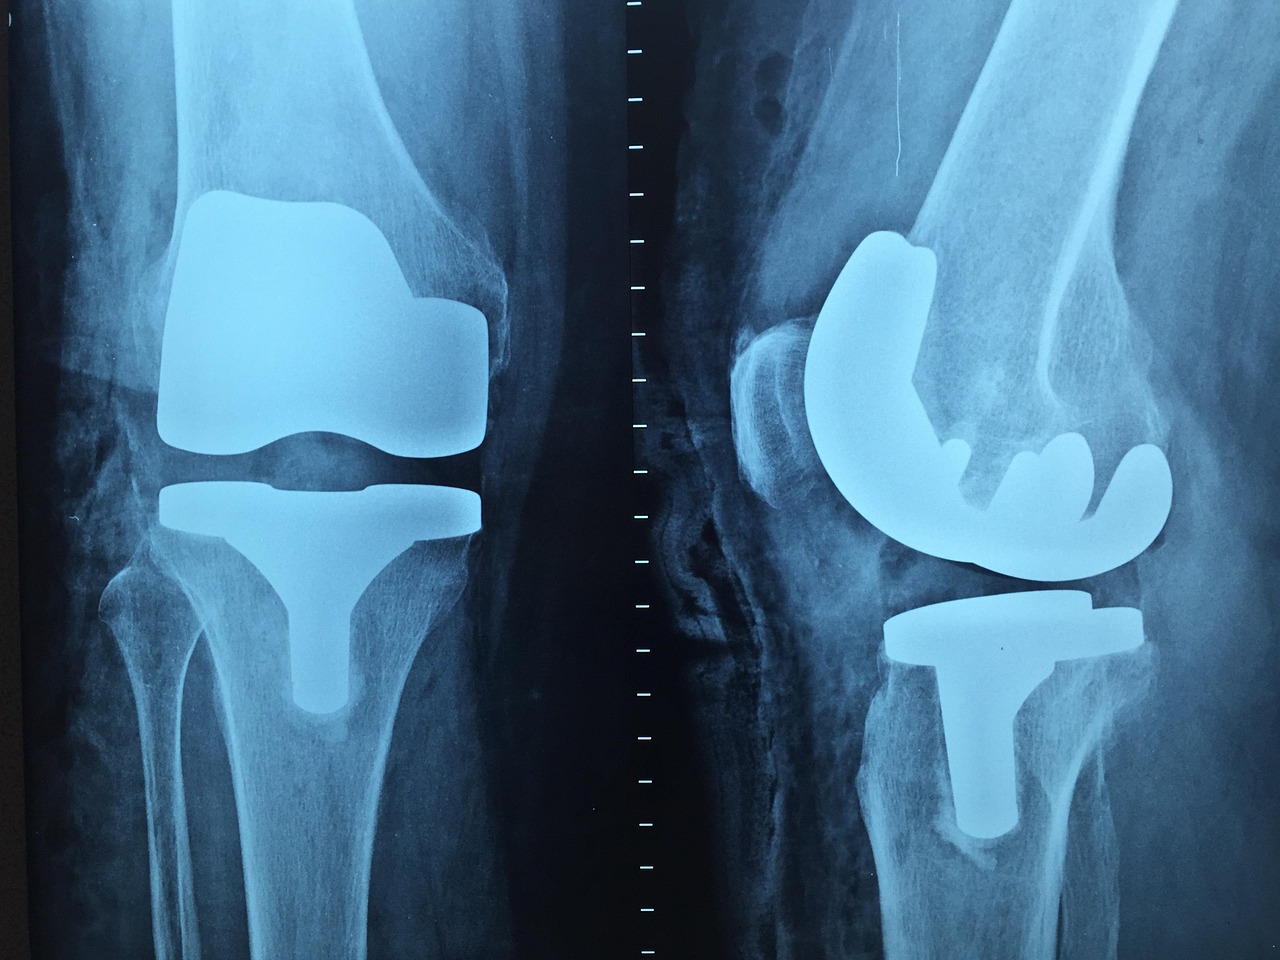

무릎 인공관절 수술은 심한 퇴행성 관절염이나 다른 질환으로 인해 무릎 관절이 손상되어 일상생활에 큰 제약을 받을 때 시행하는 수술입니다. 통증 경감과 관절 기능 회복을 통해 삶의 질을 현저히 높일 수 있는 효과적인 치료법이죠.

단순히 통증이 있다고 해서 모두 지원 대상이 되는 것이 아니라, 방사선 검사 결과(연골 손상 정도, 관절 간격 협착 등)와 임상 증상(통증 정도, 보행 능력 제한 등)을 종합적으로 고려하여 수술의 적합성이 판단되어야 합니다. 이는 불필요한 수술을 방지하고 꼭 필요한 환자에게 혜택을 주기 위함입니다.